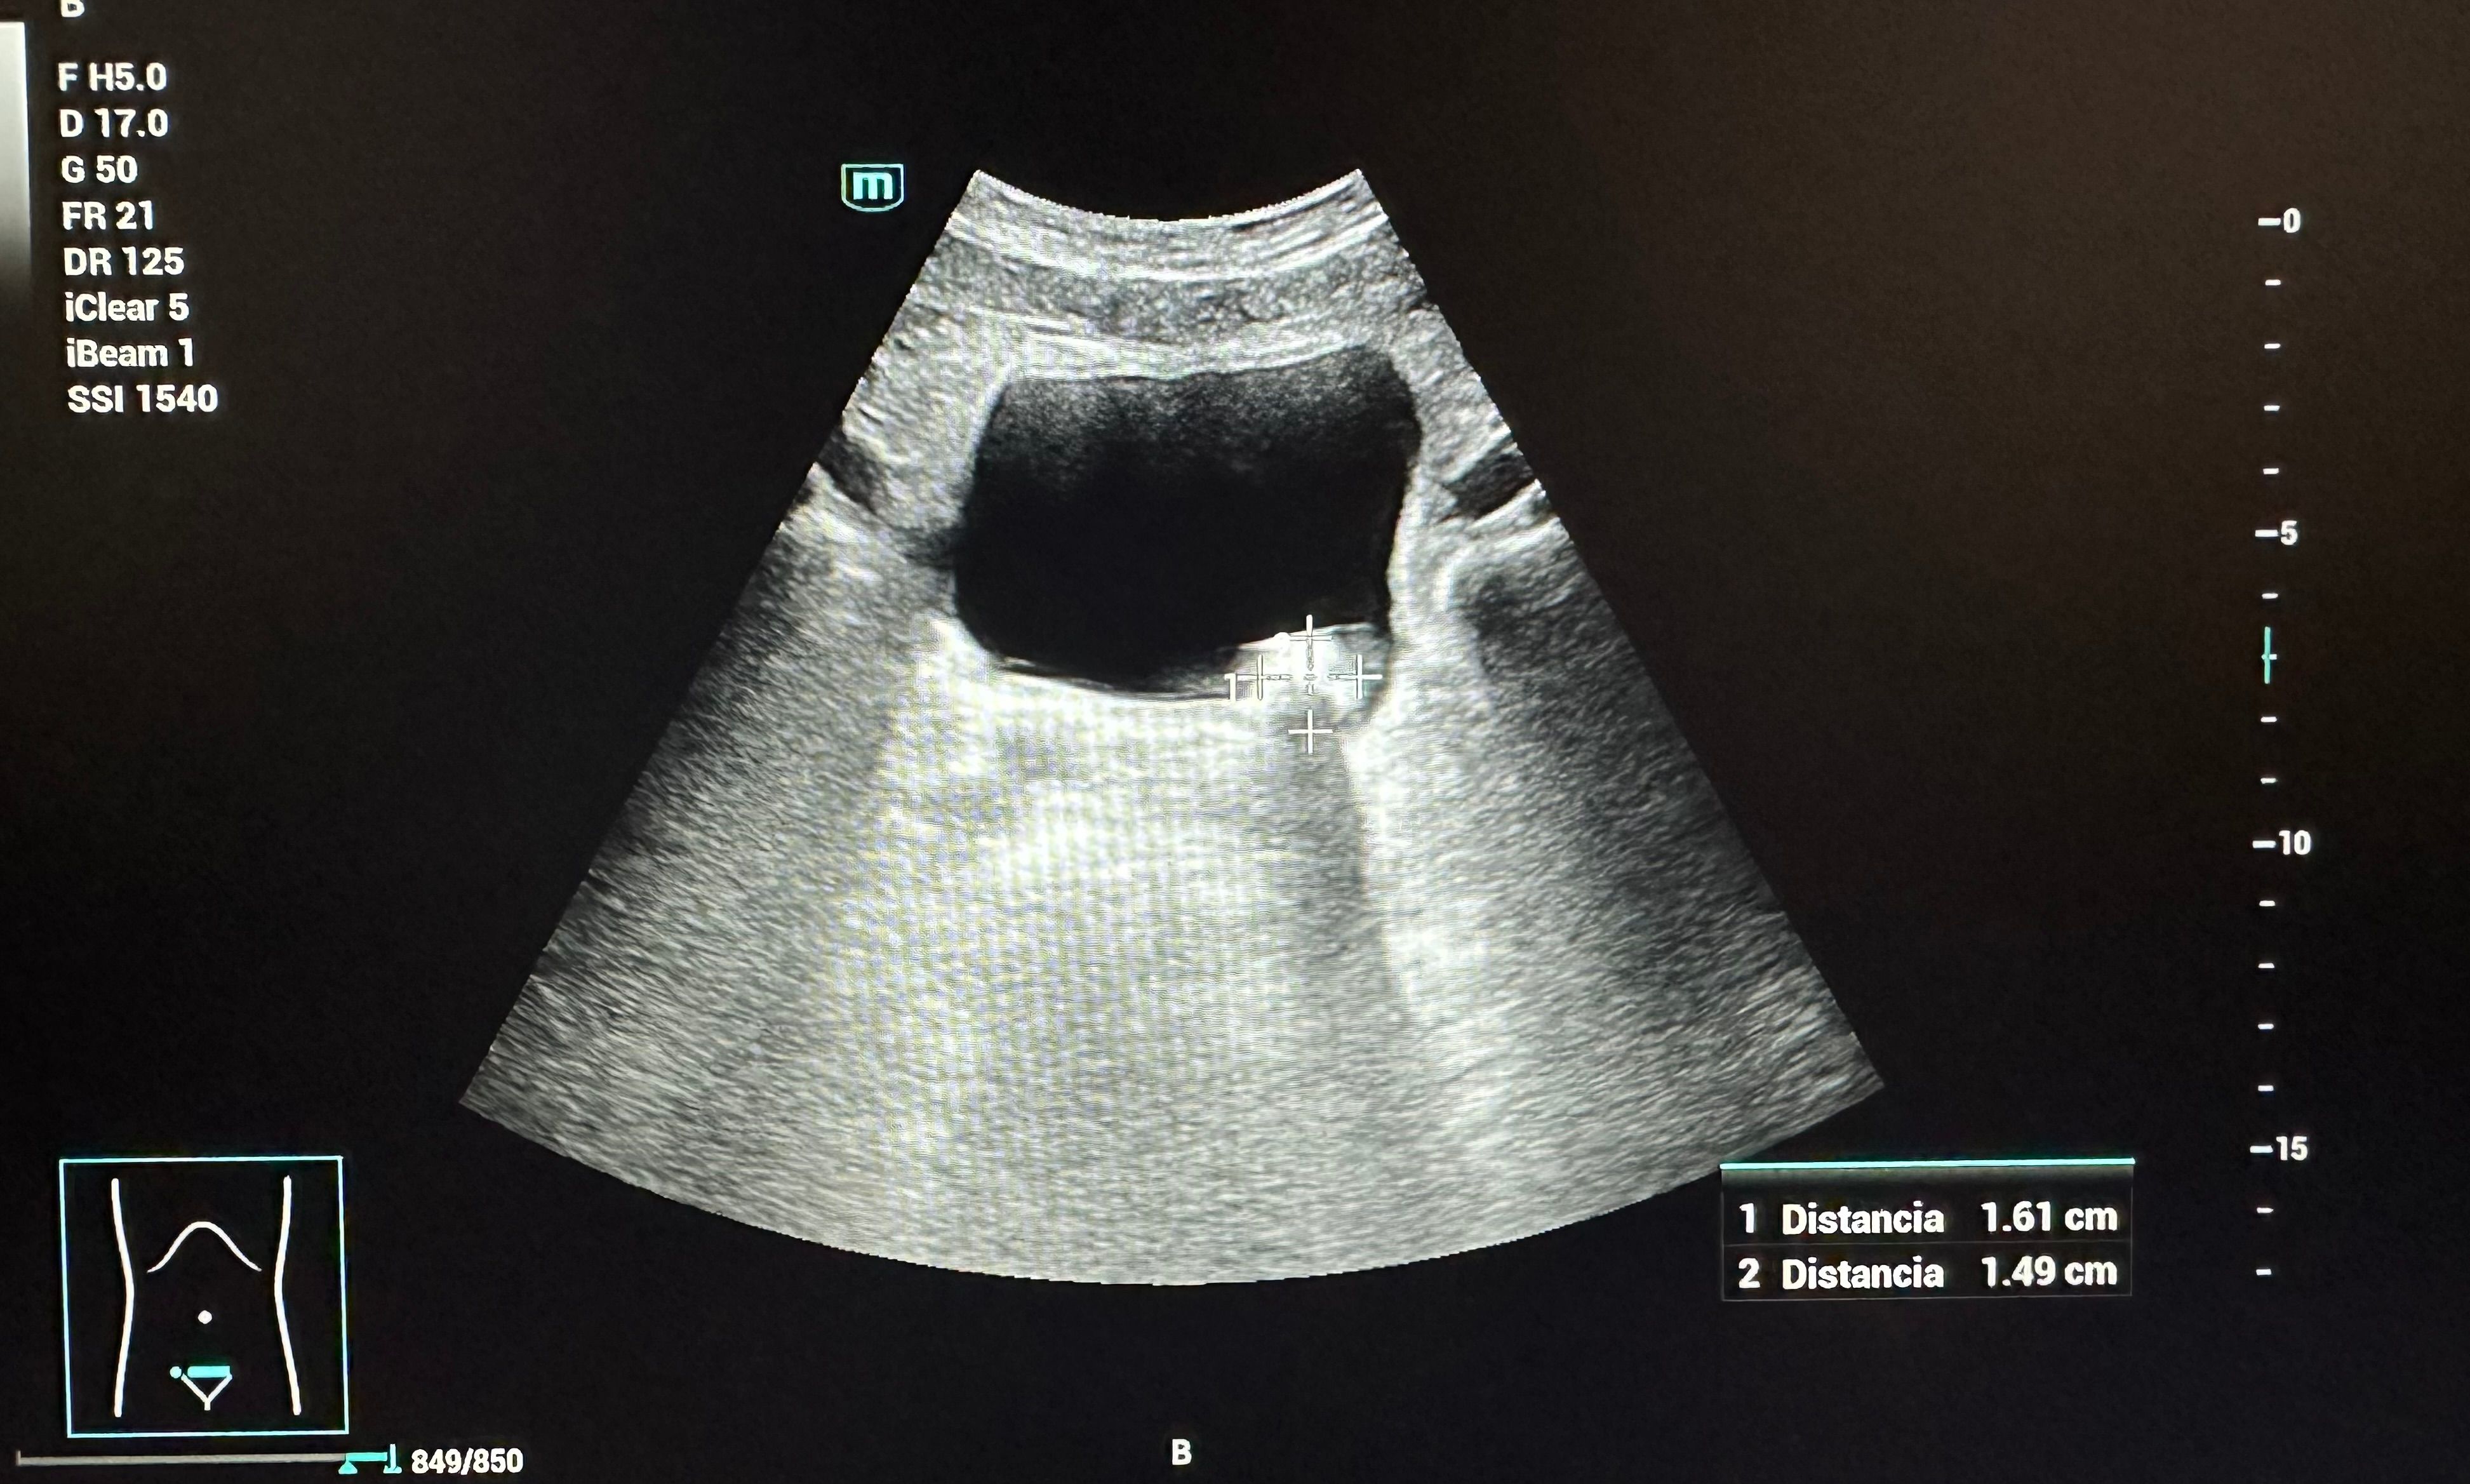

Hallazgos ecográficos

En la ecografía realizada se observó una litiasis vesical de 1,6 cm x 1,5 cm. No se observó dilatación de la vía urinaria ni otros hallazgos relevantes que sugirieran complicaciones agudas.